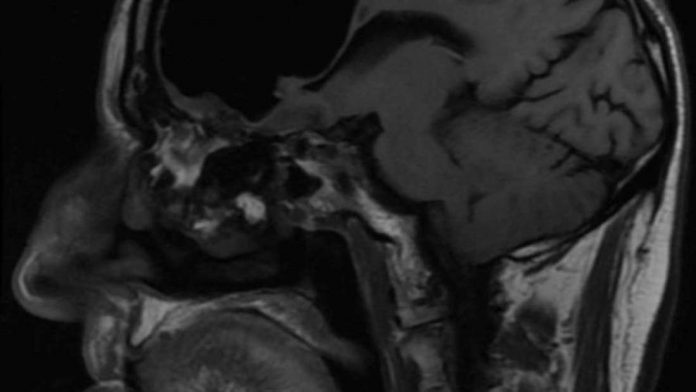

Perhaps nothing too strange for a man of his age, but further investigations revealed these symptoms were a red flag signaling much bigger problems. Brain-imaging CT scans revealed a strange 9-centimeter (3.5-inch) void in his skull just behind his forehead in the right frontal lobe.

Although the scan appeared to show part of his brain was missing, it later transpired the doctors were looking at a massive air-filled cavity, what’s known as a pneumatocoele. His brain was still there, it had just been squished out of the way by the pocket of air.